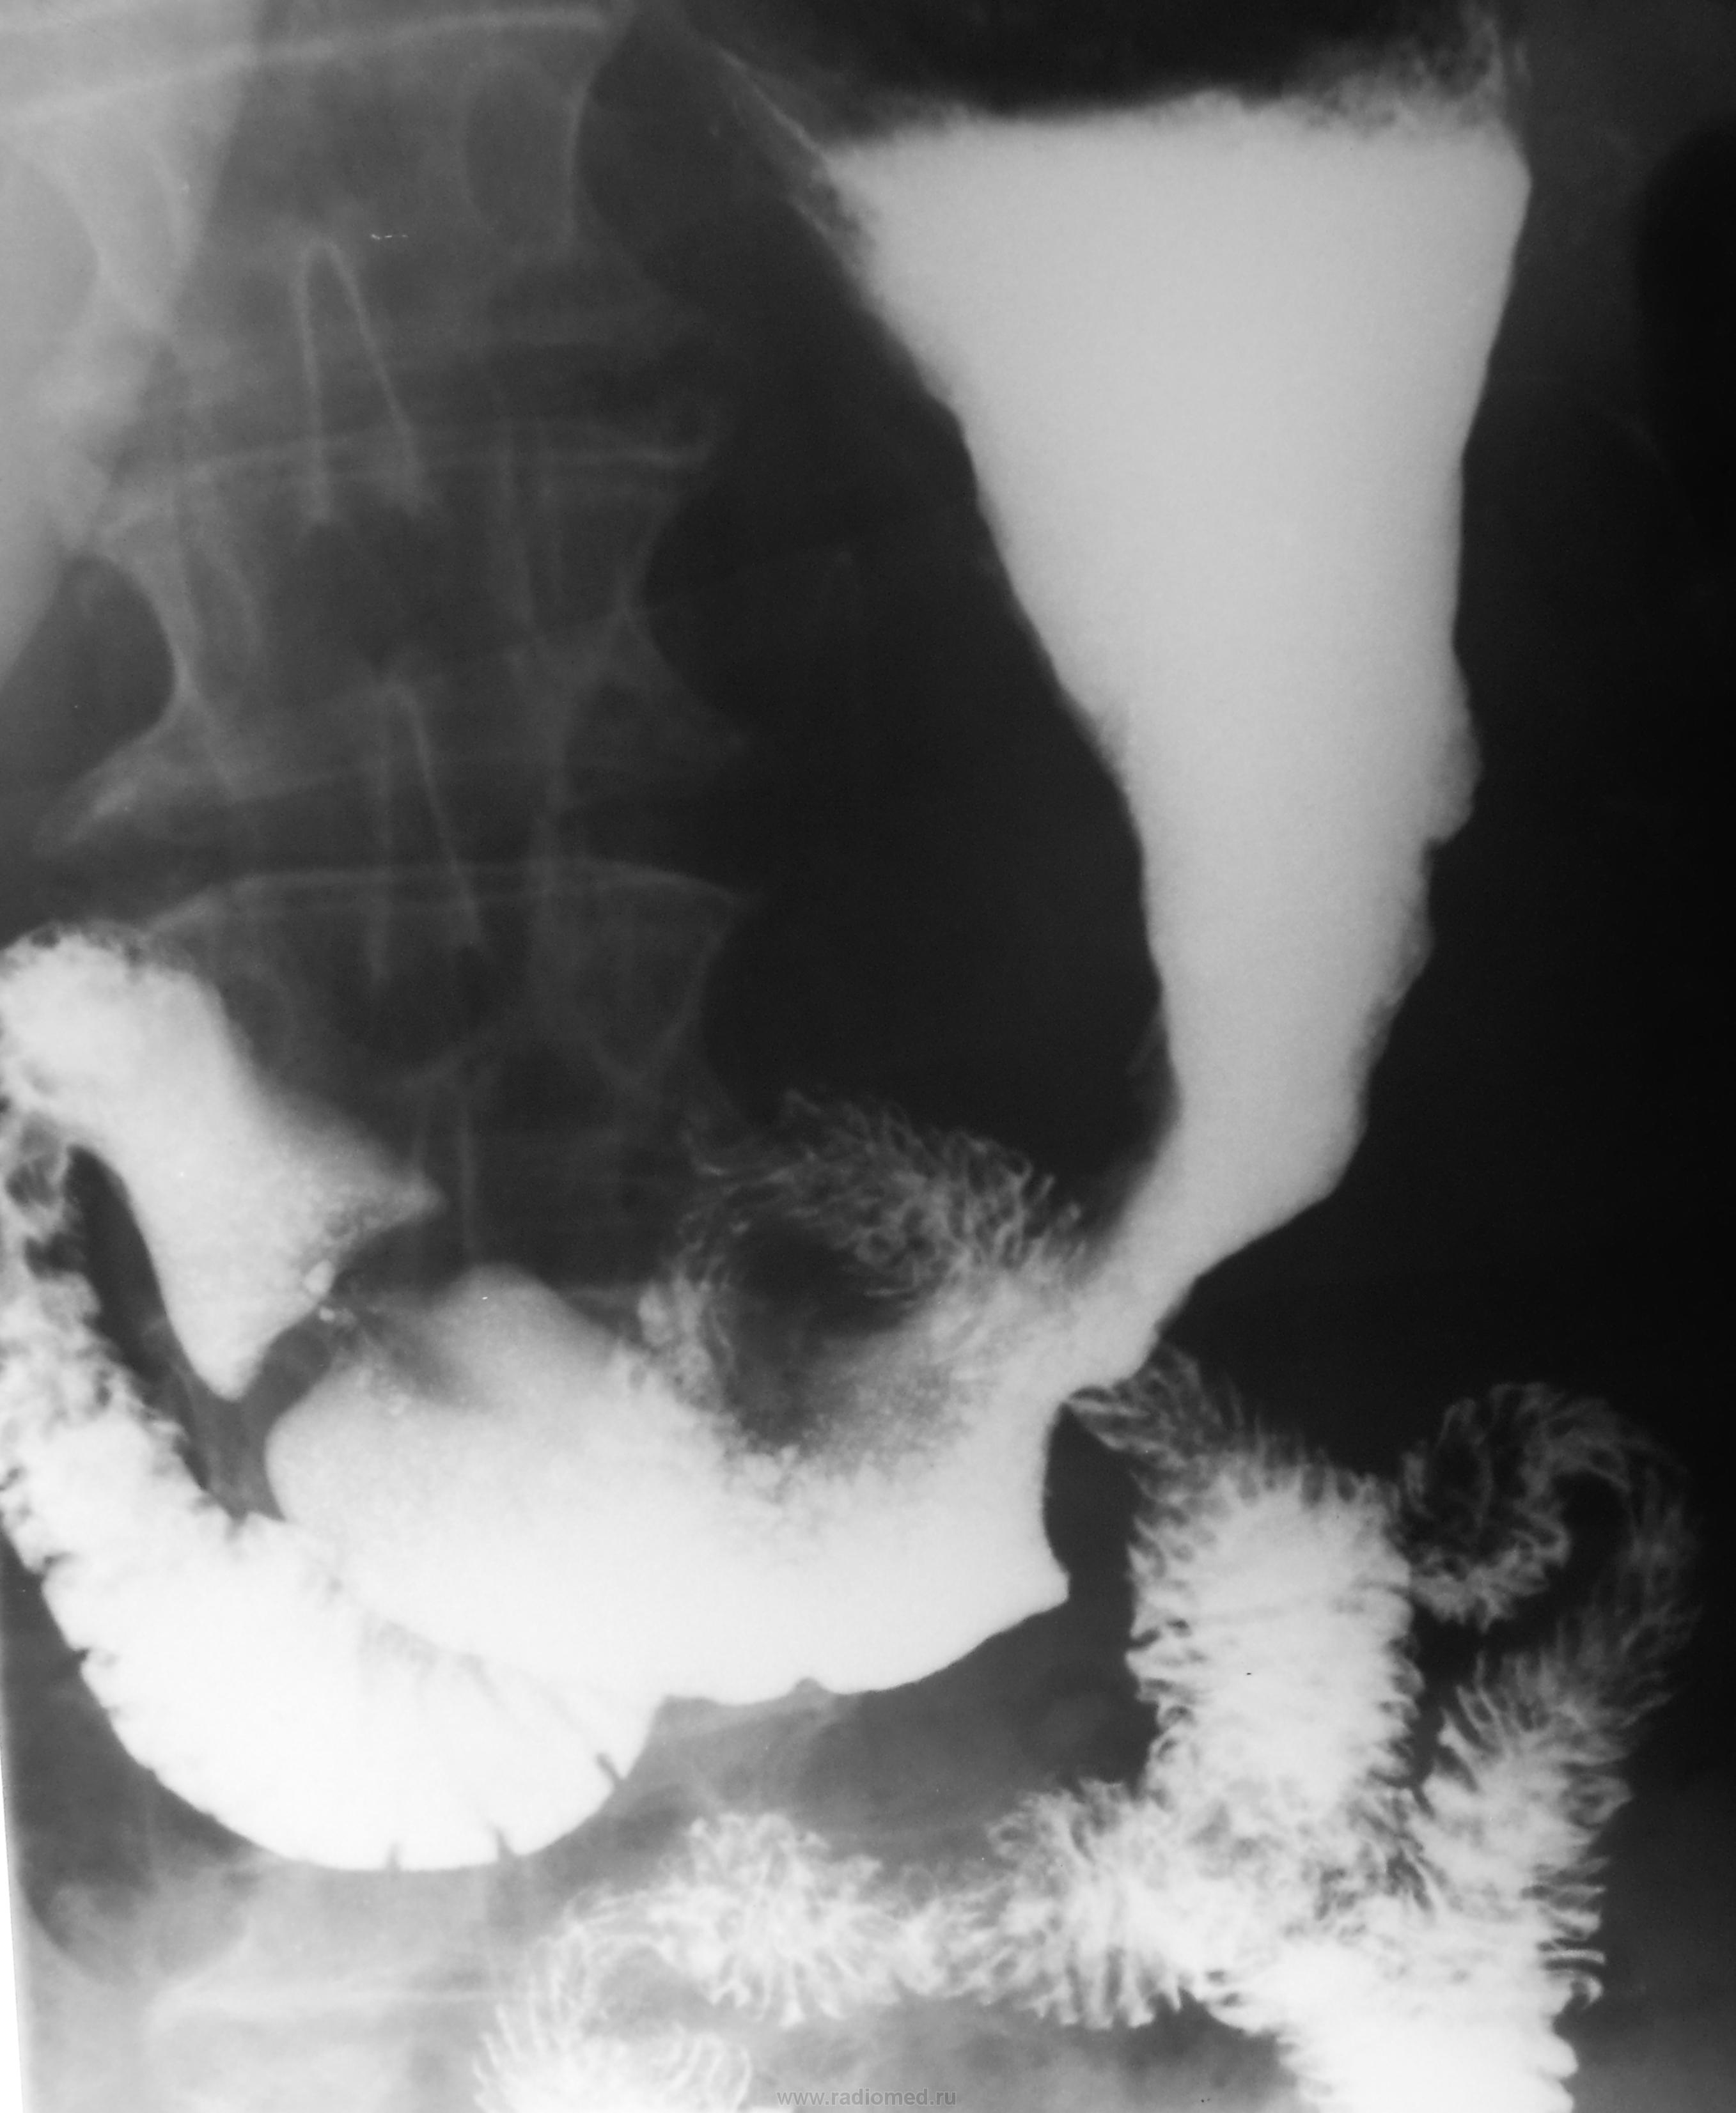

Судя по-всему, поражены отделы от субкардии до антрального.

+ еще дивертикул 12-типерстной кишки.

Конечно, на дивертикул можно было и сделать серию, но в данном, конкретном случае дивертикул не у дел..., при таком распространенном раковом поражении...

Но, отчасти Вы правы, ибо на рентгенологическое исследование пациентка была направлена с диагнозом...- "Дивертикул пищевода".